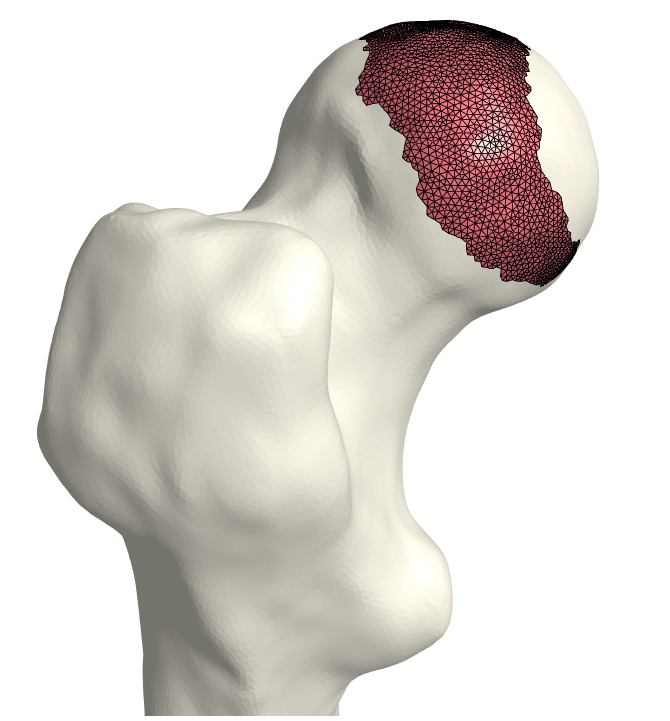

That is, we extrude each vertex 𝐯jsubscript𝐯𝑗\mathbf{v}_{j} in the direction of its normal by the displacement wjsubscript𝑤𝑗w_{j}. As a final step, we invert the bone-attached face normals before collecting the three disjoint sets of faces and vertices into a single mesh, (𝒱C,C)subscript𝒱𝐶subscript𝐶(\mathcal{V}_{C},\mathcal{F}_{C}). Observe in Fig. 3 the cartilage sub-surfaces combined into a single mesh.

Refer to caption

(a) Femoral cartilage.

(b) Femoral cartilage.

(c) Pelvic cartilage.

Figure 3: The final cartilage generated by our method for a femur (a), (b) and a pelvis (c). Notice how the cartilage aligns with the anatomical lines.